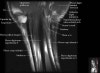

- Sagittal section

Sagittal T1 evaluates the tendons, bone marrow and relationships between the osseous structures.